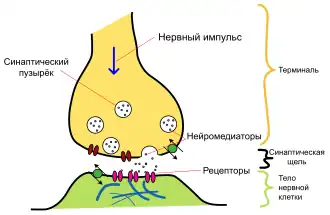

Нейроны substantia nigra получают многочисленные проекции от нервных клеток базальных ганглиев. В свою очередь они образуют синаптические связи с нейронами ретикулярных ядер ствола мозга и базальных ганглиев[8]. Нейроны, составляющие компактный отдел, имеют полихимическую природу. В ретикулярной части чёрной субстанции выявлено большое количество нейронов, содержащих ГАМК, в компактной части — дофамин. Кроме того, в чёрной субстанции имеются различные нейропептиды. Данная структура широко связана с различными отделами центральной нервной системы. Но особенно тесно чёрная субстанция функционально связана с базальными ганглиями (полосатое тело и бледный шар), а также анатомически — со зрительными буграми.

Pars compacta чёрной субстанции состоит из дофаминергических нейронов. Эти нейроны афферентные и связываются с другими структурами мозга: хвостатым ядром и скорлупой, которые входят в группу под названием полосатое тело. Такая связь позволяет высвобождать дофамин в указанных структурах.

Чёрная субстанция играет весьма значимую роль в развитии многих заболеваний, включая болезнь Паркинсона. В чёрной субстанции расположены тела нейронов, аксоны которых, составляющие нигростриарный путь, проходят через ножки мозга, внутреннюю капсулу и оканчиваются в неостриатуме в виде широкого сплетения терминальных микровезикул с высоким содержанием дофамина. Именно этот путь является тем местом в мозге, поражение которого приводит к формированию синдрома паркинсонизма[15].

Известно, что повышение уровня дофамина участвует в развитии шизофрении. Однако большая дискуссия продолжается и по сей день вокруг этой теории, которая широко известна как «дофаминовая теория шизофрении». Несмотря на разногласия, антагонисты дофамина остаются стандартными средствами лечения шизофрении. Эти антагонисты включают препараты первого поколения (типичные) антипсихотики, такие как производные бутирофенона, фенотиазина и тиоксантена. Эти препараты были в значительной степени заменены препаратами второго поколения (атипичными нейролептиками), такими как клозапин и рисперидон. Эти препараты не действуют на дофамин-продуцирующие нейроны и на рецепторы постсинаптических нейронов.

С угнетением дофаминергической передачи в нигростриарной системе (блокадой дофаминовых Д2-рецепторов[18]) при использовании нейролептиков связывают развитие экстрапирамидных побочных эффектов[19]: паркинсонизма, дистонии, акатизии, поздней дискинезии и др.

Различные независимые исследования показали, что многие лица, страдающие шизофренией, имеют повышенный поток дофамина и серотонина, поступающего в постсинаптические нейроны мозга.[20][21][22][23] Эти нейромедиаторы являются частью так называемой «системы вознаграждения» и вырабатываются в больших количествах во время позитивного по представлению пациента опыта типа секса, наркотиков, алкоголя, вкусной еды, а также стимуляторов ассоциированных с ними.[24] Нейробиологические эксперименты показали, что даже воспоминания о позитивном опыте могут увеличить уровень дофамина[25][26][27], поэтому данный нейромедиатор используется мозгом для оценки и мотивации, закрепляя важные для выживания и продолжения рода действия.[28] Например, мозг лабораторных мышей вырабатывал дофамин уже даже во время предвкушения ожидаемого удовольствия.[29] Однако некоторые пациенты умышленно перенапрягают эту систему вознаграждения, искусственно вызывая приятные для них воспоминания и мысли снова и снова, поскольку таким образом натурально производятся нейромедиаторы хорошего настроения, теряя при этом самоконтроль.[23] Это похоже на наркотическую зависимость,[30] ведь практически все наркотики прямо или косвенно нацелены на систему вознаграждения мозга и насыщают его структуры дофамином[31][32]. Если пациент продолжает перестимулировать свою систему вознаграждения, то постепенно мозг адаптируется к чрезмерному потоку дофамина, производя меньше гормона и уменьшая количество рецепторов в системе вознаграждения[33]. В результате химическое воздействие на мозг уменьшается, понижая способность пациента наслаждаться вещами, от которых он раньше получал удовольствие[32]. Это понижение заставляет пациента, зависимого от дофамина, усиливать свою «мыслительную деятельность» пытаясь привести уровень нейромедиаторов в нормальное для него состояние[23] — этот эффект известен в фармакологии как толерантность. Дальнейшее привыкание может постепенно привести к очень тяжелым изменениям в нейронах и других структурах мозга, и потенциально может в долговременной перспективе нанести серьёзный ущерб здоровью мозга[34]. Современные антипсихотические препараты нацелены на блокировку функций дофамина. Но, к сожалению, эта блокировка иногда также вызывает и приступы депрессии, что может усилить зависимое поведение пациента[35]. Когнитивно-поведенческая психотерапия (КПТ), проводимая профессиональным психологом, также может помочь пациентам эффективно контролировать свои настойчивые мысли, поднять самооценку, понять причины депрессии и объяснить им долговременные негативные последствия дофаминовой зависимости[36][37]. «Дофаминовая теория» шизофрении стала очень популярной в психиатрии в связи с эффективностью атипичных антипсихотиков, блокирующих нейромедиаторы, однако многие психологи не поддерживают эту теорию, считая её «упрощенной», также существует несколько различных течений внутри сторонников теории[20].

Химические воздействия и изменения чёрной субстанции, происходящие на молекулярном уровне, играют важную роль в таких областях медицины, как нейрофармакология и токсикология. Различные соединения, такие как леводопа и МФТП (метилфенилтетрагидропиридин), используются для лечения и изучения болезни Паркинсона, а также многие другие препараты оказывают влияние на substantia nigra.

Кокаин

Как и кокаин, амфетамины увеличивают концентрацию дофамина в синаптической щели, тем самым усиливая реакцию постсинаптических нейронов. Кроме того, как и кокаин, вызывают нарушения функций дофамина, что способствует привыканию.